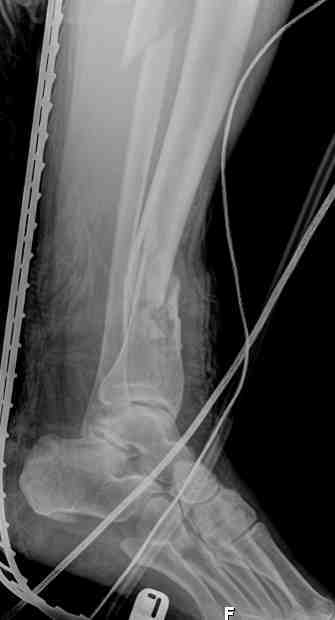

Выше представлены рентгенограммы открытого оскольчатого перелома нижней трети голени

X-rays of Compound Comminuted # Distal/3 Lt Tibia

В нижнем ряду представлены рентгенограммы после окончательной репозиции.

And final reduction after Hexapod program has been finished

Одновременное и точное исправление многоплоскостной деформации является очень важным моментом, который трудно даётся при применении аппарата Илизарова, особенно при сочетании с ротационной деформацией. В этом случае гексаподный аппарат Илизарова незаменим.

Simultaneous and exact correction of multilane deformities combined with rotation is very important and difficult to accept at application of Ilizarov apparatus. In these cases Ilizarov hexapod apparatus is irreplaceable.